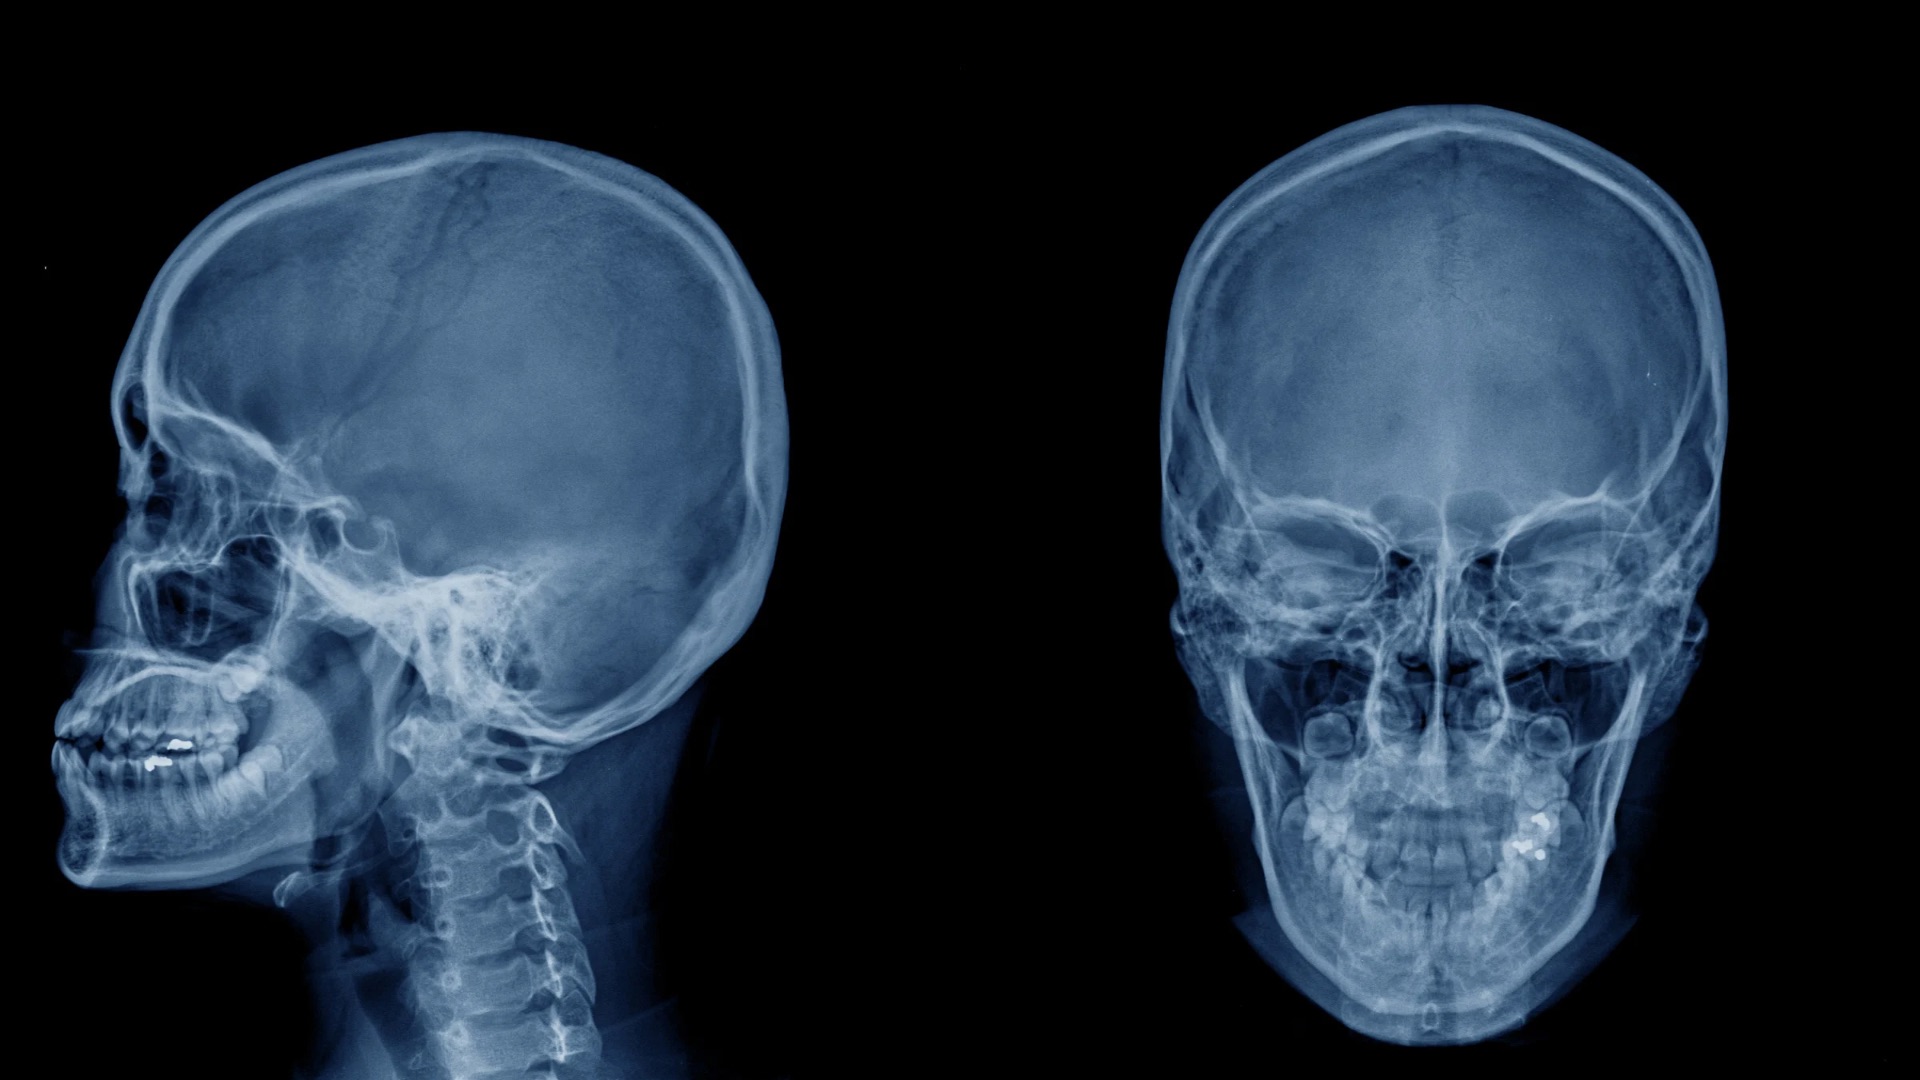

Unlock the power of accurate diagnosis with— the ultimate online course for dentists, dental students, and internationally trained professionals. Designed for new grads, foreign-trained dentists, and even dental teams, this course helps you confidently read and interpret bitewings, periapicals, and panoramic X-rays. Learn to detect dental caries, periodontal disease, periapical infections, and rare anomalies with hundreds of real-world radiographs. Whether you're preparing to practice in Canada, U.K., USA, Australia, or New Zealand, or simply want to reduce clinical errors and legal risks, this course gives you the skills to diagnose accurately, intervene effectively, or refer wisely. ✅ Identify what you can treat — and when to refer ✅ Avoid missed diagnoses and reduce liability ✅ Sharpen your clinical judgment with case-based learning ✅ Boost your confidence with expert interpretation techniques With radiographic accuracy at the core of dental success, this course is your key to safer, smarter, and more confident practice. Enroll now and level up your diagnostic skills.